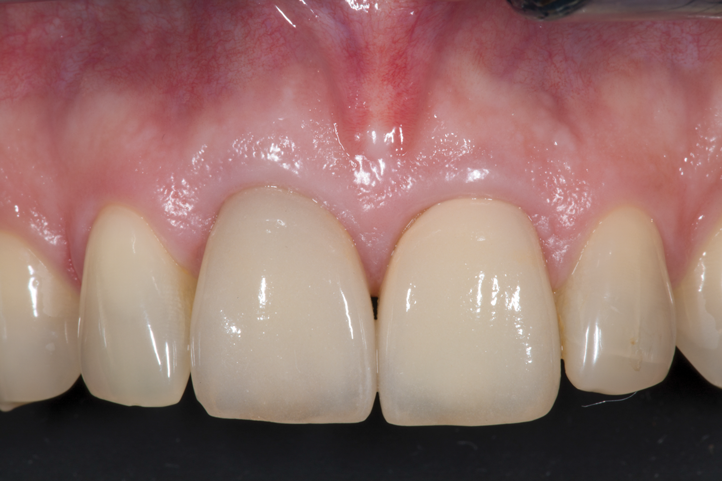

Fig 12. Implant placement No. 27 (4:3) after preparation of the root for PET protocol, demonstrating the ability to ideally place the implant within the newly prepared PET socket and maintain the integrity of the surrounding soft tissues.

Figure 12

Fig 14. Final restoration on implant placed into position No. 27 (4:3) with PET protocol, illustrating the final esthetic outcome of this implant and associated restoration in a thin phenotype.

Figure 14